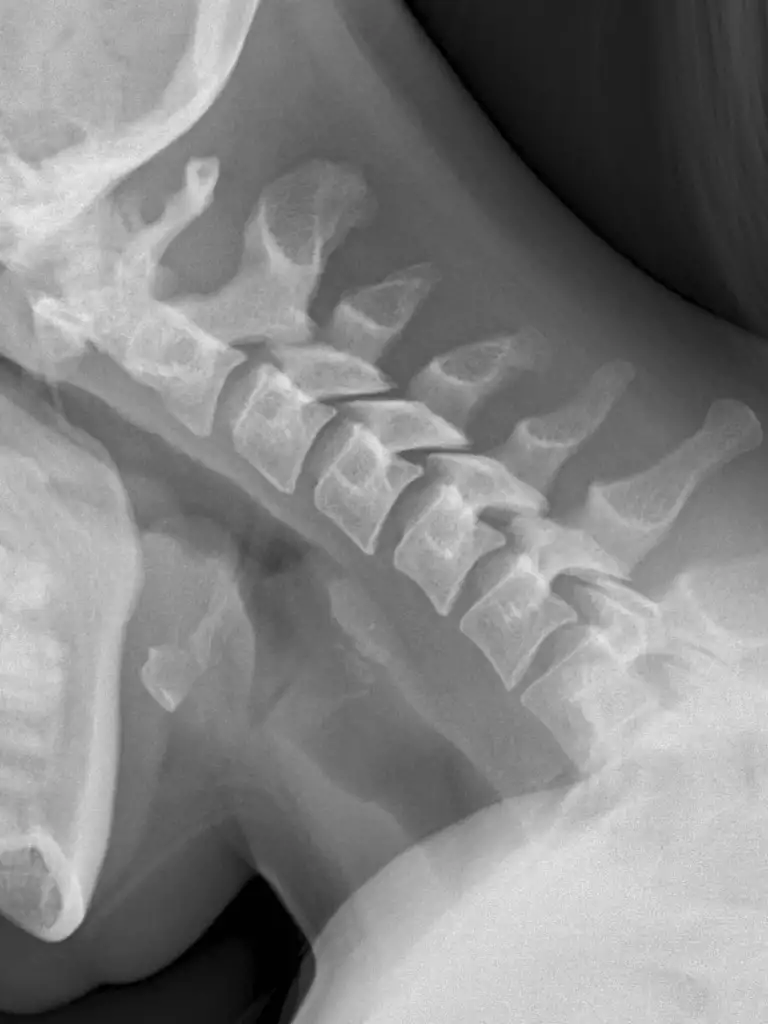

X-Ray Cervical Spine Flexion View

An X-ray of the Cervical Spine Flexion View test is used to visualize the neck's first seven vertebrae (C1-C7) of the spinal column (backbone). It helps visualize intervertebral discs and the surrounding skin and muscles. Flexion-rays identify ligament damage not visible on static scans. These x-rays can detect cervical spine injuries.

This test determines the source of long-lasting neck or upper back pain, any spinal injury or fracture, and suspected spine tumors or infections.